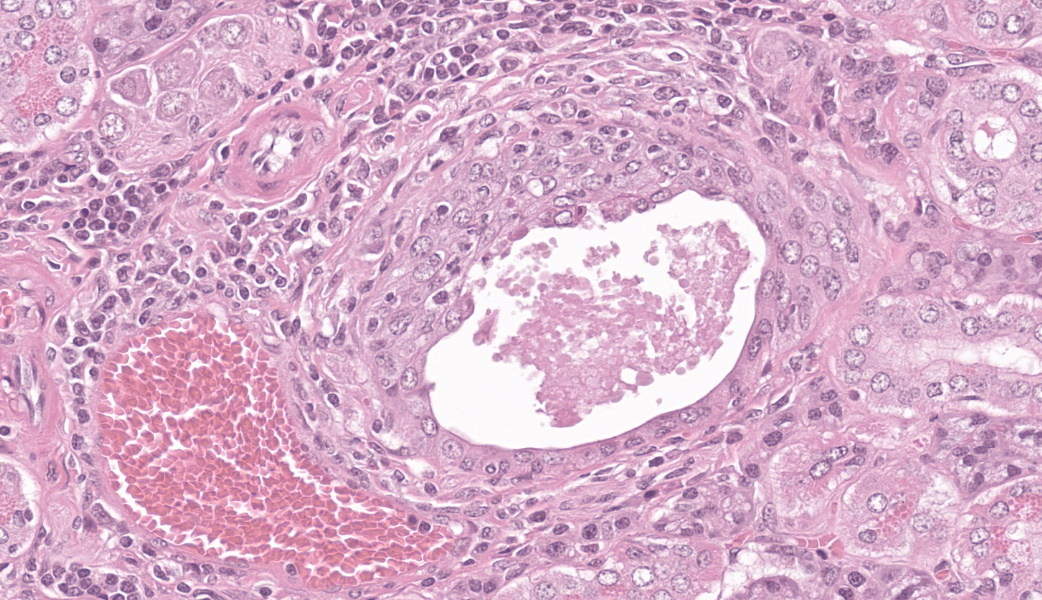

Microscopic Description:

Few acinar and stromal cells with markedly enlarged nuclei and abundant cytoplasm (cytomegaly) with 8-12 µm eosinophilic intranuclear inclusions were scattered throughout the submandibular salivary gland with accompanying lymphoplasmacytic infiltration in several regions.p

Sialoadenitis, multifocal, subacute to chronic, mild with epithelial and stromal cytomegaly and intranuclear inclusions (cytomegalovirus)p

The most frequently encountered lesions occur in the submandibular salivary glands and rarely in the parotid glands, with excretion in saliva serving as the primary means of transmission through grooming and biting activities. Typical histological findings include eosinophilic intranuclear and intracytoplasmic inclusions in acinar epithelial cells with cytomegaly and interstitial lymphoplasmacytic inflammation.6 Intranuclear inclusions result from viral DNA replication within the nuclei of infected cells, while intracytoplasmic inclusions represent replication processes that occur in the cytoplasm, including production of the capsid protein.8

Salivary gland: Sialoadenitis, lymphoplasmacytic, chronic, multifocal, mild, with epithelial karyomegaly and intranuclear viral inclusions.

This case provided an excellent example of a truly classic lesion that every pathologist should be able to recognize and should come to the forefront of the mind when presented with a slide of murine salivary gland. The contributor provided a great comment on cytomegaloviruses and covered much of what was taught during this case in conference.

While the tissue identification and diagnosis in this case were straightforward, there were some other structures on the slide that served as an excellent reminder of mouse anatomy. Mammary tissue in mice is extensive and can be as far cranial as the submandibular area. Mammary glands are frequently seen in association with the submandibular salivary gland, often hanging out in the subcutaneous tissues.